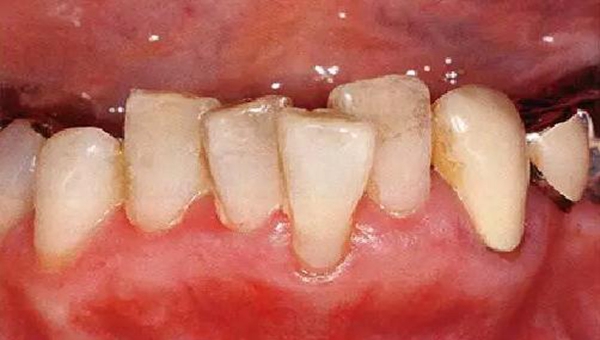

●牙列異常引起的附著喪失